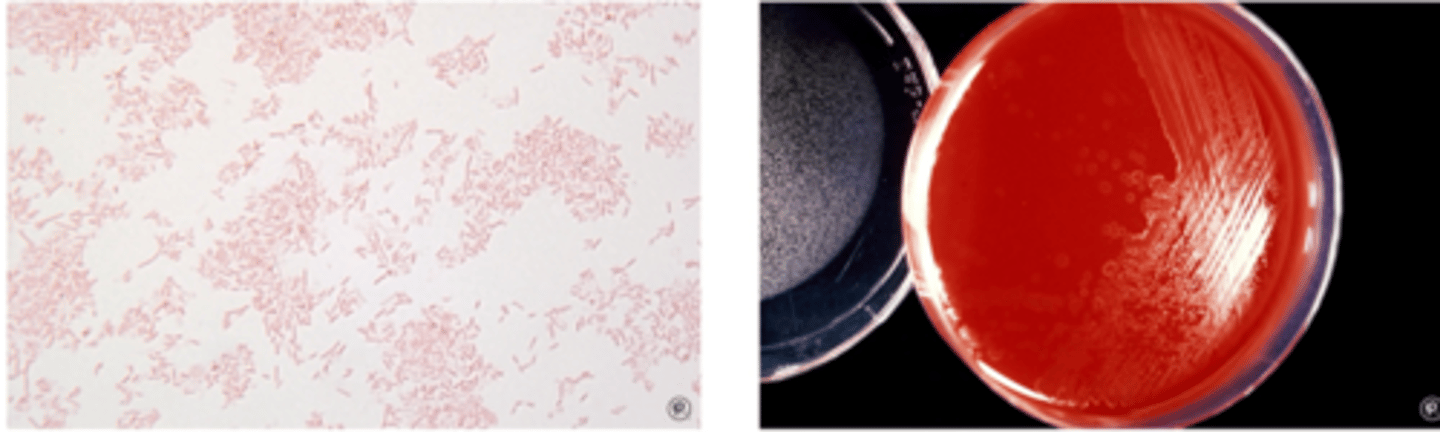

Clostridium perfringens